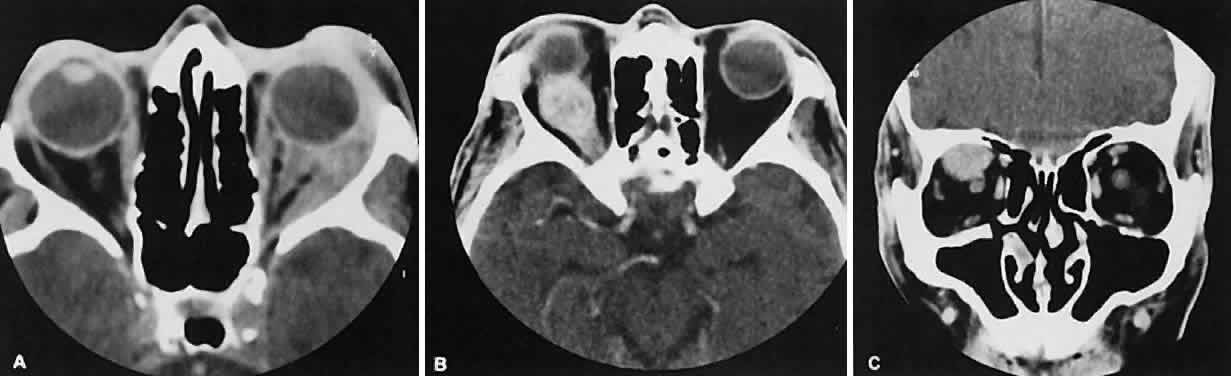

the inferior orbital fissure near the apex. Lesions that appear to change

size or shape from the axial view to the coronal view also have turned

out to represent a varix based on our experience (Fig. 2). Arterial lesions may either have high or low flow. The high-flow lesions are carotid cavernous sinus fistulas and result from a direct communication between the carotid artery and the cavernous sinus. These arise spontaneously or as a result of trauma. The orbit is involved as an innocent bystander, because all signs and symptoms of orbital involvement follow from the retrograde transmission of increased venous pressure from the cavernous sinus. EOMs generally are enlarged, as is the SOV. The ipsilateral cavernous sinus also is enlarged. Intercommunication between the cavernous sinuses also may account for the occasional bilateral findings. Low-flow lesions result from increased blood flow through the cavernous sinus, but the intracavernous carotid artery itself is intact (Fig. 3). These typically are dural-cavernous sinus fistulas. A high index of suspicion may be required to diagnose these, but a fairly stereotyped presentation is a unilateral red-eyed glaucoma with proptosis. Abduction weakness also may be present. Enlargement of one or more EOMs along with an enlarged SOV are noted with CT scanning. A small lesion may escape detection with CT scanning and require high-resolution MRI or even selective internal and external carotid angiography for diagnosis if a high degree of clinical suspicion exists. In a patient with a known dural fistula, a sudden and dramatic deterioration in the clinical picture may be seen with a thrombosis of the SOV.11 The radiographic picture, at least regarding the CT appearance, probably will not change. MRI can nicely show the thrombosis in the SOV.